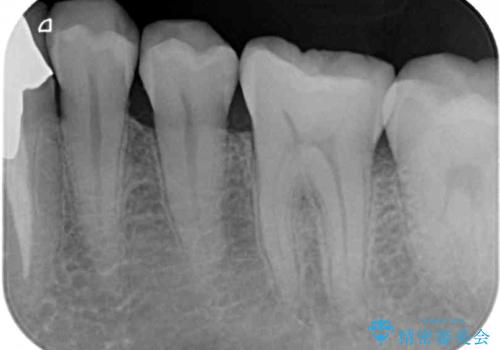

- 張り出している骨隆起による話しにくさを気にして来院された患者様です。

目視でも大きいと分かる骨隆起が認められたため、歯肉を切開した上で切除することとしました。

また、付近の歯に大きなむし歯が認められたため、セラミックインレーによる修復治療も行うこととしました。